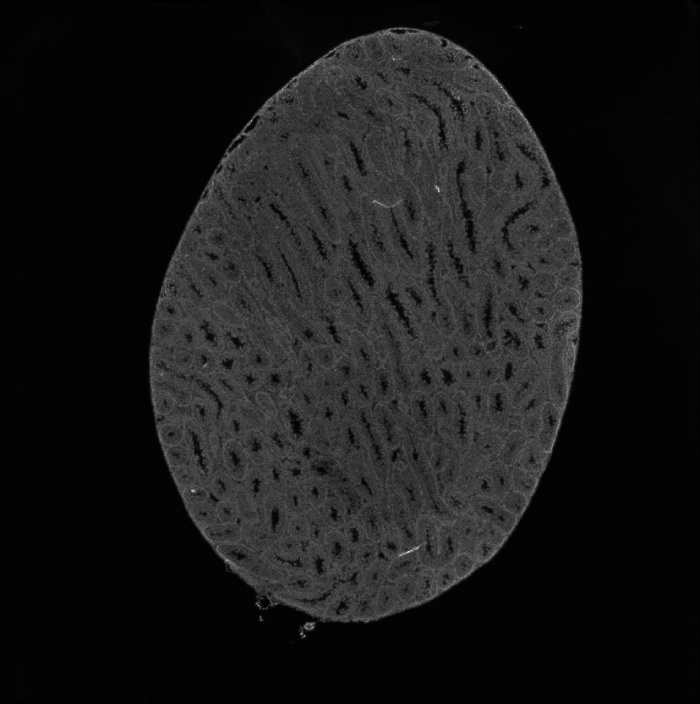

組織umi-count統(tǒng)計(jì)圖

圖2 組織UMI count統(tǒng)計(jì)圖